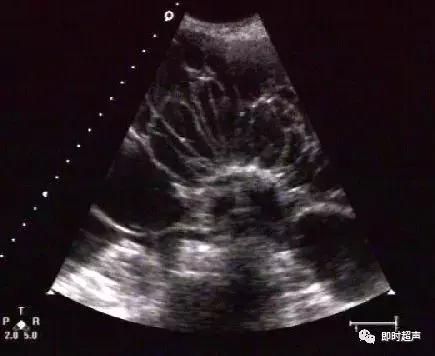

卵巢子宫内膜异位囊肿的超声表现为囊内密集点状回声,但其内也可出现带状间隔及团块状稍高回声,其与周围组织可粘连,囊壁厚而毛糙,较高回声较多沉积在中后部,呈絮状,较松散,加压探头或随访可见形态改变。患者一般有痛经病史。卵巢畸胎瘤的细密点状比内膜异位囊肿点状更细、更密、更高,团块状高回声亦更致密、更均匀、更高,且具清晰边界并常伴声影。易与囊样型和混合型卵巢畸胎瘤混淆,同时需要警惕两者并存的情况。

浆液性囊腺瘤:单房或多房囊腺瘤边界清晰,囊壁薄而完整,内壁光滑,纤细分隔光滑均匀。乳突状囊腺瘤在囊内壁上突起乳头,其囊壁、囊内间隔及乳突上可见细条状血流。

单纯性囊肿:卵泡囊肿、黄体囊肿、附件炎性囊肿、卵巢冠囊肿、阔韧带囊肿等,可通称为单纯性囊肿。一般内部透声好,无明显光点,超声表现为宫旁附件区囊性肿物,壁薄,内无回声。而卵巢畸胎瘤表现为单房状瘤内无回声时,可见囊壁局限性增厚,伴回声增强。